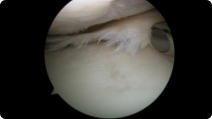

This page contains arthroscopic and radiography images of joint injuries and conditions, and the surgical repairs performed by Dr. Joshua Landau.

Arthroscopic image of an ACL tear Arthroscopic image of an ACL reconstruction

ACL Tear

ACL Reconstruction